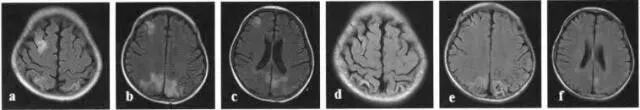

图片

所有患者通过干细胞疗法干预后结果显示:与治疗前比较治疗后血液中白细胞,中性粒细胞,淋巴细胞计数增加,肝肾功能水平均升高,但均在正常范围内。

头部 MRl T2 Flare像:a-c是治疗前;d-f是治疗后8个月

免疫检测未发现异常,治疗后脑脊液中白细胞和红细胞数量增加,有利于修复受损神经系统。唯一出现副反应是头疼或发热,但两者均在短期内会自动消退。